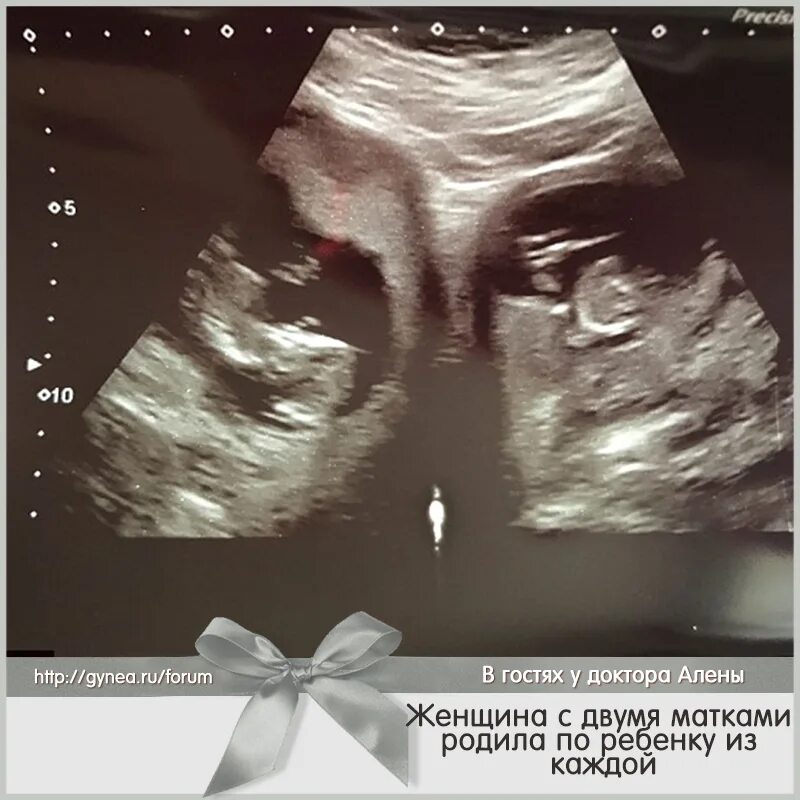

Может быть две матки